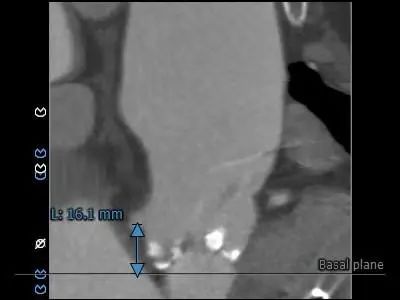

主动脉根部测量

瓣上测量

1.Type 0 型二叶瓣,瓣叶增厚,双侧瓣叶边缘连续条状钙化,瓣膜锚定难度适中,瓣膜植入受两侧钙化挤压存在移位风险及瓣周漏风险。

2.冠脉开口高度可,未见冗长瓣叶,结合瓦氏窦、STJ内径综合预估,冠脉风险适中。